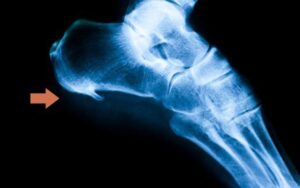

- Espolón calcáneo: Es un crecimiento óseo anormal en el talón que puede causar dolor y molestias.

En una de nuestras clínicas Podoactiva tratamos a un paciente de 44 años, con diagnóstico de espolón calcáneo y refiriendo un fuerte dolor al apoyar el talón en el suelo.

Tras analizar las radiografías, nuestros especialistas comprueban que existen calcificaciones en la inserción de la fascia plantar y en el tendón de Aquiles. El paciente presenta un acortamiento muscular de todo el sistema aquíleo calcáneo plantar que ha ido produciendo microrroturas de las estructuras. El organismo ha generado las calcificaciones como un método de regeneración.